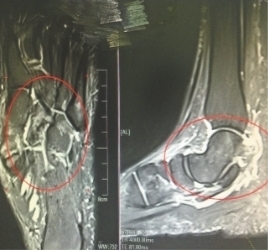

拍片显示张小姐踝关节有积液

骨科医生检查发现,张小姐存在踝关节积液,足部跖骨出现严重的骨损伤,这与患者长时间穿裸露脚踝的牛仔裤有关。该院中医科阮景云医师介绍,脚踝皮下脂肪较少,保暖性能较差,天气寒冷时,露出脚踝、膝盖的穿戴方式导致脚部长期暴露在冷空气中,长此以往,低温会阻碍关节气血循环,导致关节疼痛、局部怕冷、伸屈受阻损伤。